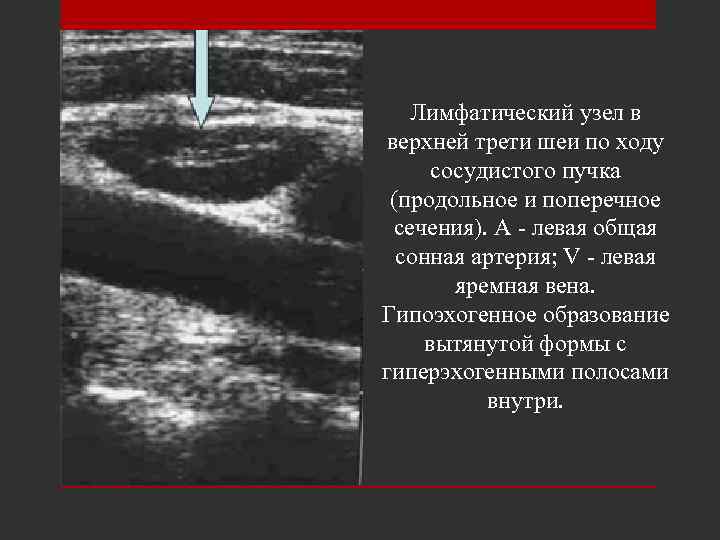

Лимфатический узел в верхней трети шеи по ходу сосудистого пучка (продольное и поперечное сечения). А - левая общая сонная артерия; V - левая яремная вена. Гипоэхогенное образование вытянутой формы с гиперэхогенными полосами внутри.